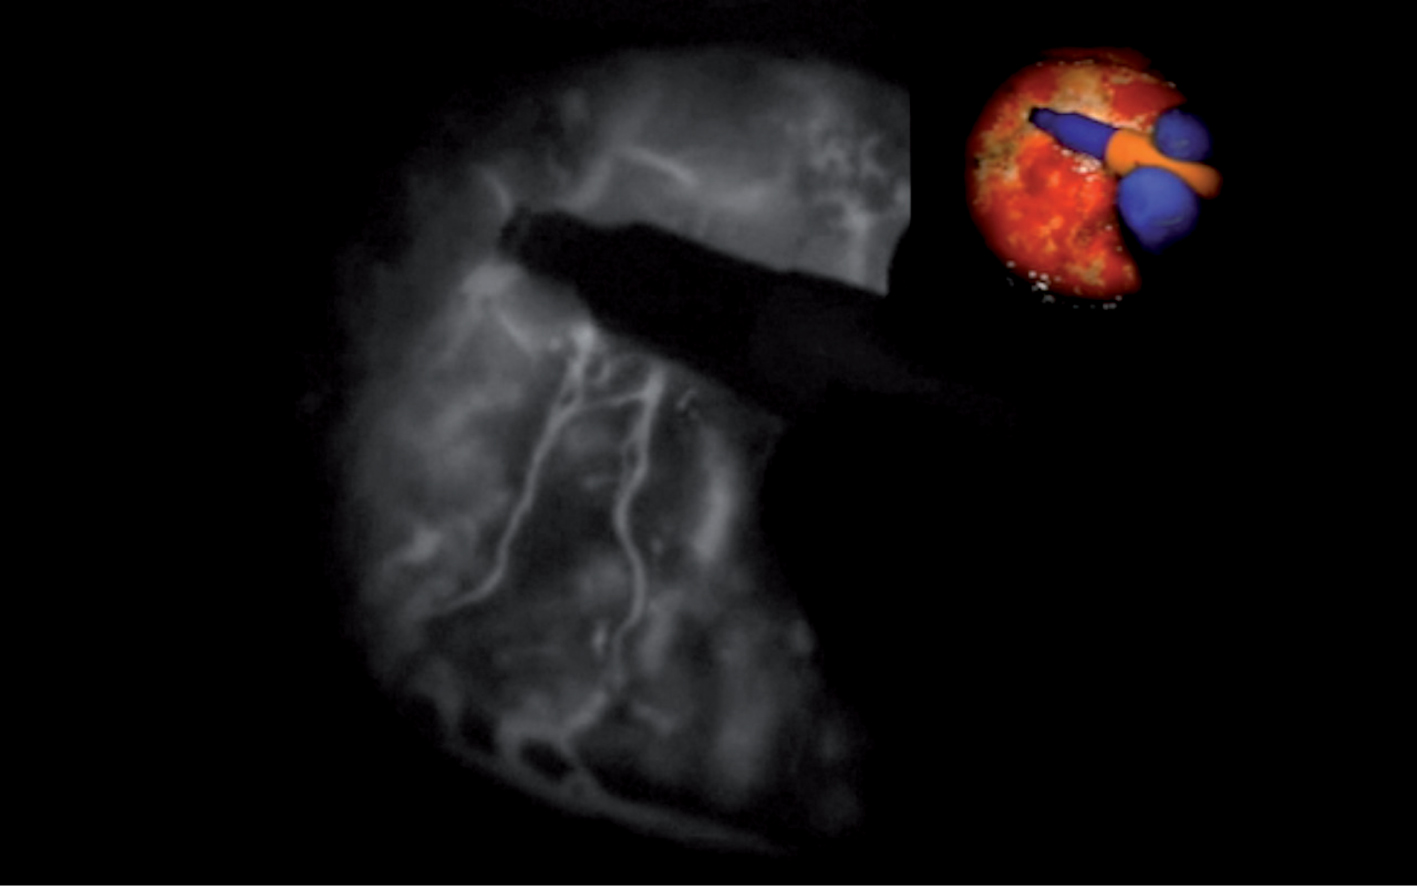

5-ALA is a natural amino acid biosynthesized from glycine and succinyl-CoA in the mitochondria. Following systemic administration, ALA in tumor cells is metabolized into protoporphyrin IX (PpIX), a photosensitizing porphyrin (35). The reason for the selective PpIX accumulation in malignant glioma is not fully understood. It is highly specific (98%) in areas of infiltrating tumor, and PpIX-levels in tumor tissue are highest at 6 h after administration (36) (Table 2). 5-ALA is an orally administered product used for visualization of high-grade glioma tissue during surgery, allowing a safer and more extensive tumor resection. Under blue light excitation (400–410 nm), the tumor tissue appears red, whereas normal tissue (including edema) does not show fluorescence (37) (Figure 1). Another fluorophore is fluorescein sodium; the major disadvantage is that the fluorescence depends on blood–brain barrier integrity, making it less specific. Fluorescein concentration will be high in all perfused tissues and vessels. If tissue is perturbed by surgery, there is unspecific extravasation of fluorescein unrelated to tumor (38). After patient intubation and before skin incision, patients receive 5–10 mg/kg of a 20% solution of sodium fluorescein, administered intravenously using a modified microscope with wavelength range of 560 nm (39) (Figure 2).

Fig 1

Figure 1 (a) Brain tumor resection using regular white light and (b) blue excitation light (400–410 nm) using 5-ALA; the tumor tissue appears red, whereas normal tissue shows no fluorescence. (Courtesy of Prof. Walter Stummer.)